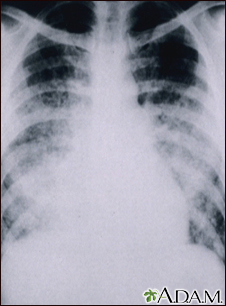

Pulmonía aguda por varicela - Rayos X de tórax

Esta radiografía muestra nubosidad en los pulmones debido a una neumonía aguda posterior a varicela. La neumonía rara vez se presenta como complicación de la varicela en los niños, pero sí ocurre en una quinta parte de los adultos.